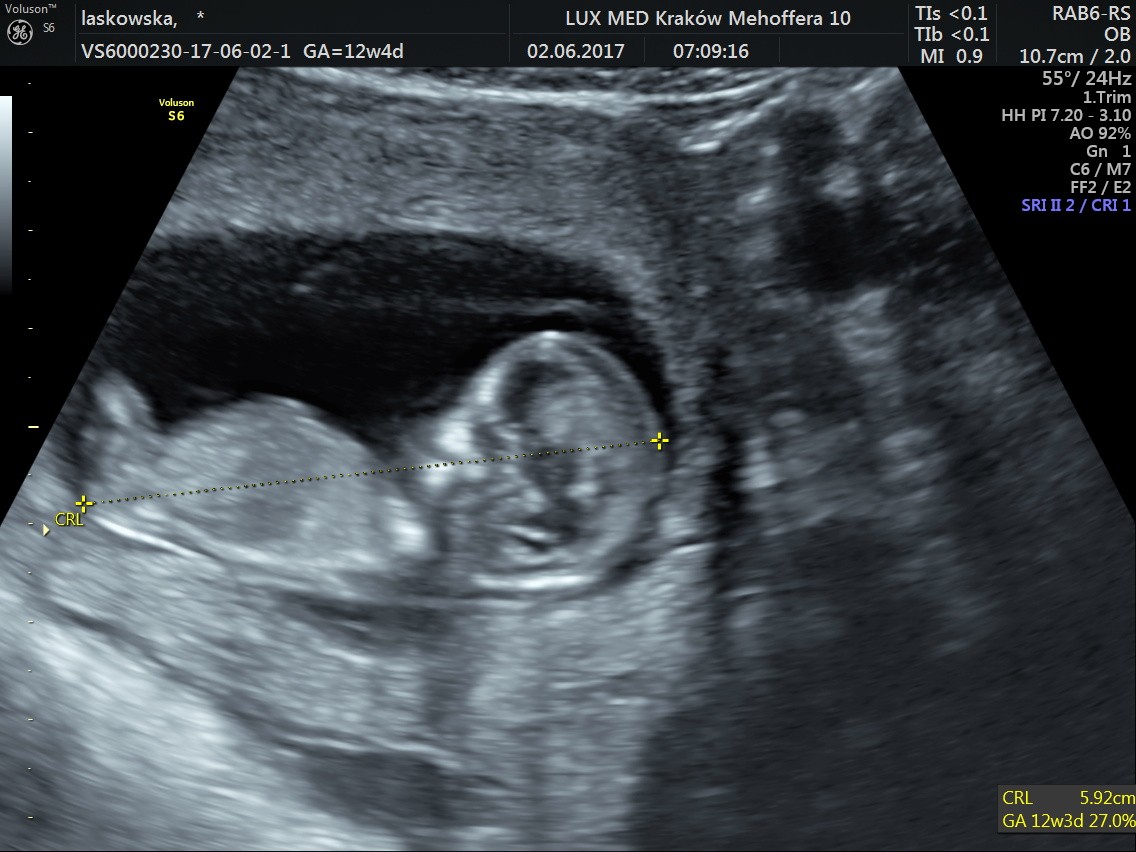

Uparte stworzenie nie chciało współpracować,bo się przecież wyspać musi, ale udało się sprawdzić co najważniejsze. Wielkość 5.92 cm, Przezierność książkowa, kość nosowa - jest, serduszko biło 160/min, móżdżek piękny, oczka najsłodsze na świecie, rączki dwie są, nóżki tak samo, widzieliśmy pęcherz i żołądeczek. Przepływy krwi w porządku. Krótko mówiąc bardzo niskie ryzyko wad genetycznych, Fistaszek jest zdrów jak rybka. Terminy nam się troszkę pozmieniały: OM 11.12.2017, USG 12.12.2017, więc zaraz zrobię poprawki w kalendarzu. Kolejna wizyta 31.07, ale będę patrzeć - może coś się zwolni parę dni wcześniej

Zdjęcia: